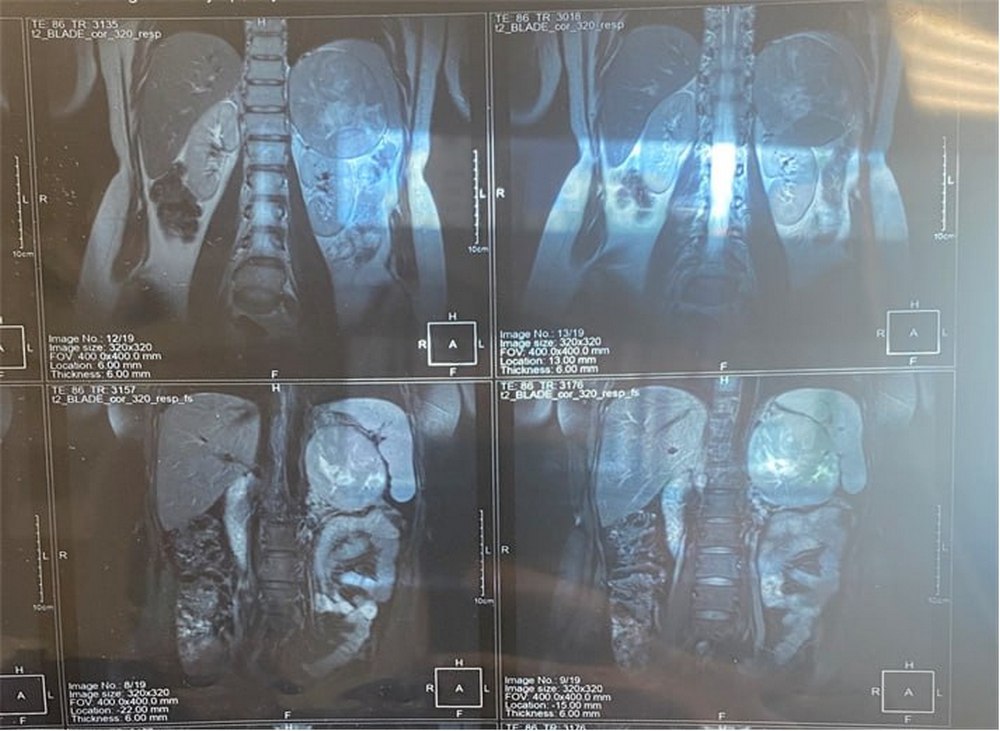

Пациенткой стала 30-летняя жительница области, поступившая с жалобами на боли в левой части живота. По данным МРТ, у женщины было выявлено объемное образование размером 94x97x140 мм, оттесняющее левую почку.